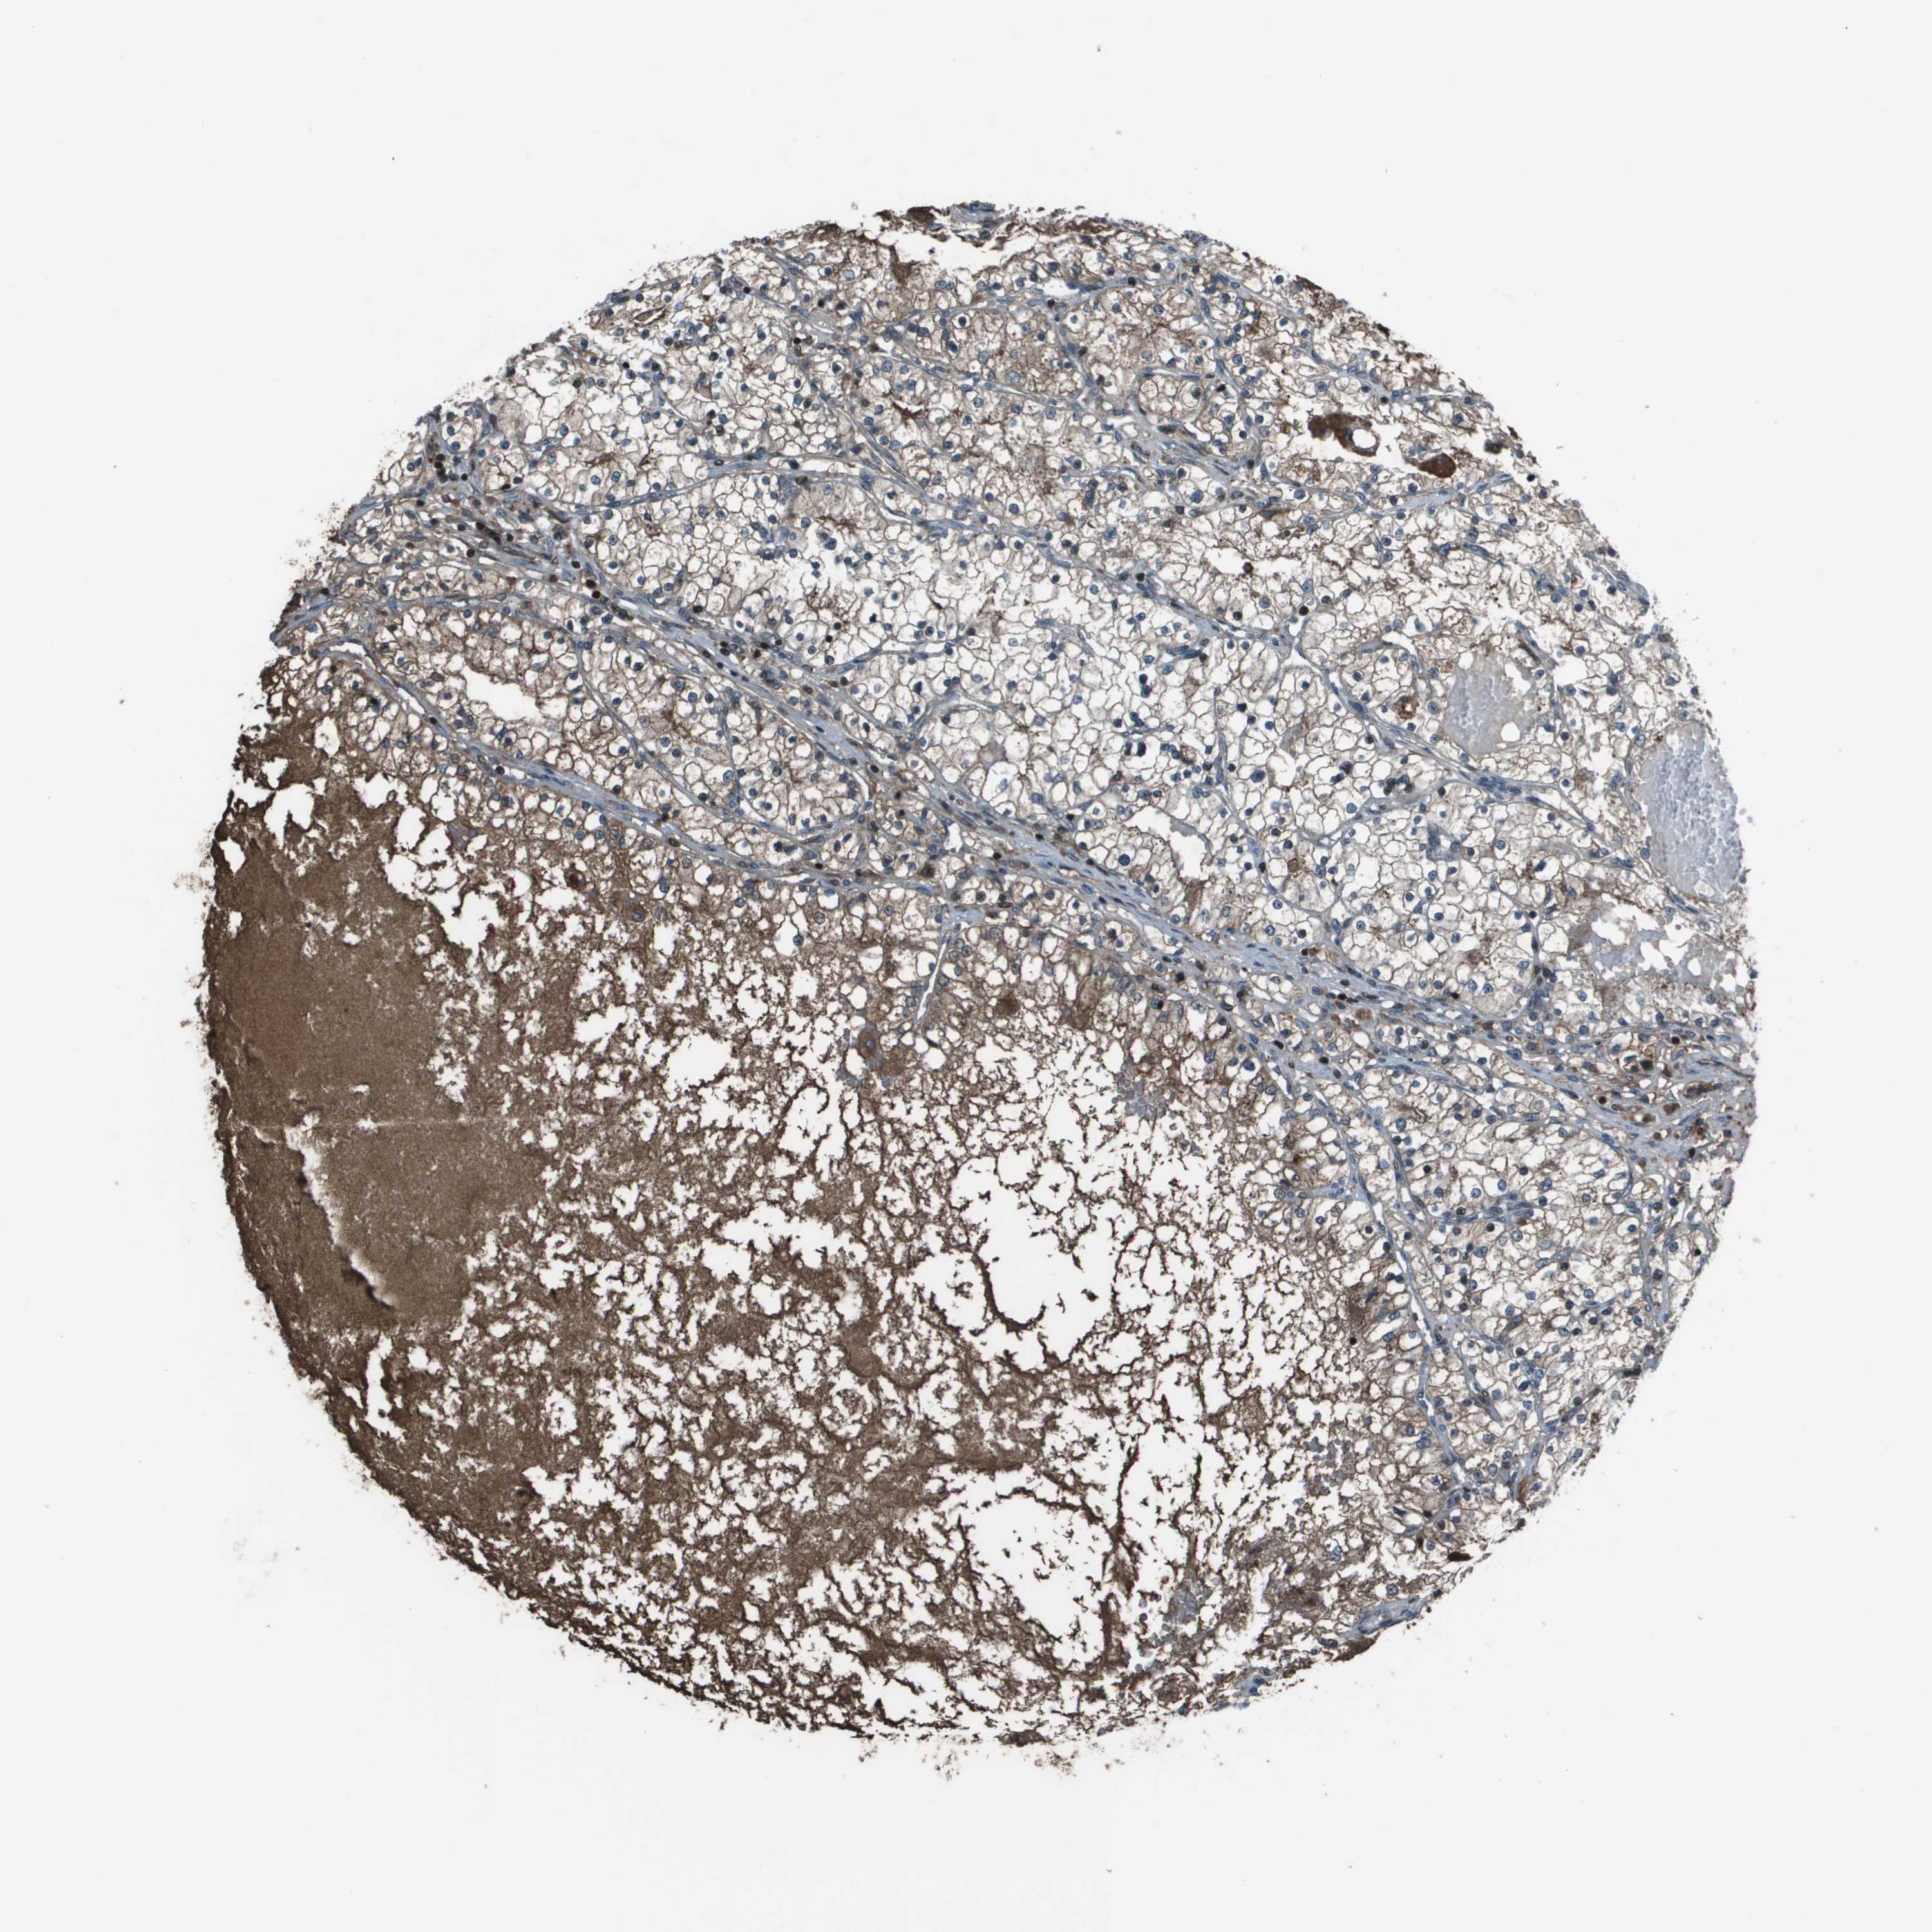

CANCER RENAL CANCER Show tissue menu

KICH TCGA KIRC TCGA KIRC VALIDATION KIRP TCGA PROTEIN RCC CPTAC PROTEIN EXPRESSION